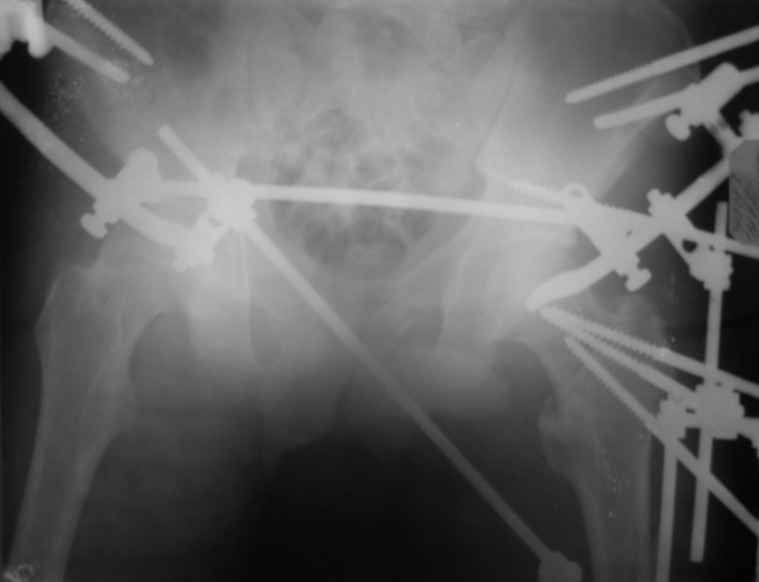

Вот снимки по свежей ситуации, парень 19 лет, длинный оскольчатый перелом бедра от шейки до в-с/3. давно уже ходит на своих ногах.

Делалось не мной (ассистировал), я на тазах "пока ещё не волшебник, а только учусь"